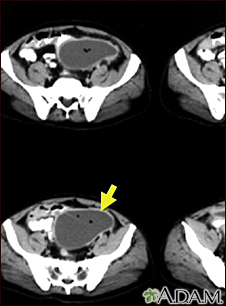

Intra-abdominal abscess - CT scan

CT scan of the pelvis showing a large intra-abdominal mass.